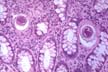

Among various amebas, the Entamoeba histolytica is the one that invades tissues in man. As long as it remains in the lumen of the colon (luminal phase), it causes no problems. When it invades the bowel wall (invasive phase) it causes a diarrhoic syndrome and may spread to the liver where it forms amebic abscesses which are usually solitary. The patient experiences pain and tenderness in that region and general symptoms with fever. The diagnosis of abscess is made with imaging techniques. The diagnosis of amebiasis is made by serological tests for amebic antibodies. The treatment is by drugs and rarely surgical. The first association of ameba with liver abscess was described by Loesch in St. Petersburg, Russia, in 1875.The figure shows clusters of ameba trophozoites in the tissue, large, up to 60 microns in diameter. This is the active mobile form. They have one small eccentric nucleus and cytoplasmic vacuoles sometimes containing red cells. The cystic form with round shape and multiple nuclei does not occur in the tissues.

Fig.147-Entamoeba histolytica

Clusters of trophozoites in the tissue, large, up to 60 microns in diameter. This is the active mobile form. They have one small eccentric nucleus and cytoplasmic vacuoles often containing red cell. The cystic form with spherical shape and multiple nuclei does not occur in the tissues.